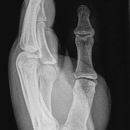

Os scaphoideum

1. Hand flach auf Kassette legen, kräftig nach lateral abduzieren. Daumen stark abspreizen.

2. Kassette mit 15° Keil unterpolstern, Daumen von Hand stark abduzieren, Handhaltung wie oben.

3. Unterarm und Hand an der radialen Seite um 45° anheben.

4. Unterarm und Hand an der ulnaren Seite um 45° anheben.

bei 1., 2. und 3.

Zentralstrahl in der Mitte der Verbindungslinie Daumensattelgelenk und Radius, sowie 1 Querfinger medialwärts.

bei 4.

In der Mitte zwischen Daumensattelgelenk und Mitte HG 2 Querfinger medialwärts.

Os scaphoideum: zwischen Daumensattelgelenk und Radius; es empfiehlt sich im Uhrzeigersinn auf der Kassette zu arbeiten.

Qualitätskriterien

Os scaphoideum soll orthograd überlagerungsfrei abgebildet sein, in den Schrägaufnahmen weitgehend überlagerungsfreie Darstellung des Os scaphoideum und der angrenzenden Handwurzelknochen. Schwer erkennbare Brüche sind oft nur in diesen Schrägaufnahmen diagnostizierbar.